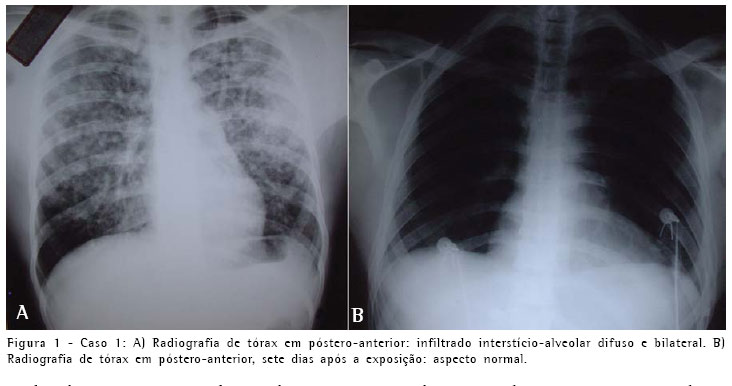

A radiografia simples do tórax, na admissão, mostrava infiltrado interstício-alveolar difuso (Figura 1). A gasometria com oxigênio por máscara facial a 8 l/min apresentou pH de 7,40, pressão arterial de oxigênio de 65 mmHg, pressão arterial de gás carbônico de 40 mmHg e saturação arterial de oxigênio de 92%. O teste rápido para o vírus da imunodeficiência humana foi negativo.

O paciente foi admitido na unidade de terapia intensiva, onde recebeu suplementação de oxigênio por máscara facial e hidrocortisona a 5mg/kg de seis em seis horas por três dias. Apresentou piora transitória do quadro clínico com aumento da dispnéia, persistência da tosse seca, retenção de gás carbônico (pressão arterial de gás carbônico de 54 mmHg), sem febre ou alteração da imagem radiológica. Foi mantido sem cobertura antibiótica e iniciou-se a administração de metilprednisolona a 1 g/dia por três dias, com melhora clínica progressiva e resolução completa da imagem radiológica no terceiro dia após o uso da metilprednisolona. O paciente recebeu prednisona a 1 mg/kg por três dias, completando dez dias de uso de corticosteróide e tornou-se assintomático. Na alta hospitalar realizou gasometria arterial, espirometria e teste de difusão do monóxido de carbono, que mostraram resultados normais.

O quadro clínico e radiológico dos três pacientes foi compatível com edema pulmonar e insuficiência respiratória aguda. A evolução revelou-se favorável e no seguimento clínico, radiológico (Figuras 1, 2 e 3) e de função pulmonar por dezoito meses não apresentaram nenhuma repercussão respiratória.